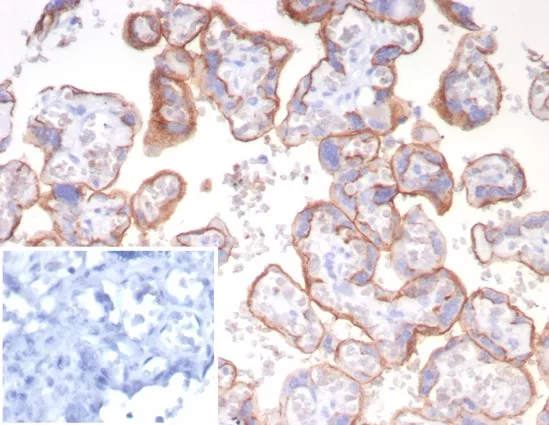

Formalin-fixed, paraffin-embedded human placenta stained with CD147 Mouse Monoclonal Antibody (BSG/7950) at 2ug/ml. Inset: PBS instead of primary antibody; secondary only negative control.